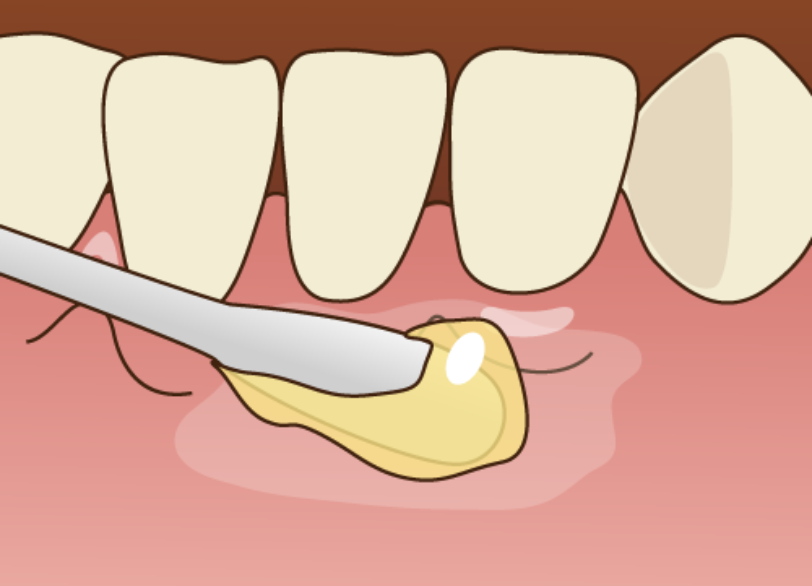

特殊な薬剤による虫歯の可視化

虫歯の部分と健康な部分の境界は肉眼では判別が難しい場合があります。

当院では必要に応じて「う蝕検知液」という虫歯に感染した部分だけを赤く染め出す特殊な薬剤を使用します。

これにより削るべき範囲を正確に見極め、健康な歯を削りすぎてしまうリスクを防ぎます。